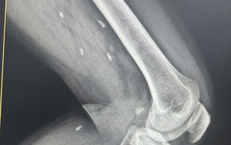

Cứu sống ngoạn mục cô gái 18 tuổi bị đa chấn thương do tai nạn giao thông

Y tế - 10/10/2025 16:23SKĐS - Sau tai nạn giao thông kinh hoàng, nữ sinh 18 tuổi được đưa vào Bệnh viện Đà Nẵng trong tình trạng nguy kịch, đa chấn thương, mất máu nhiều. Cuộc “chạy đua với tử thần” bắt đầu, các bác sĩ kích hoạt báo động đỏ, giành giật từng phút để giữ lại sự sống mong manh cho em.